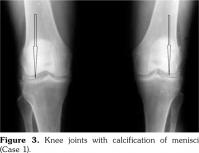

On examination, there was swelling and painful restriction of movement in her right knee. Imaging revealed calcification of cartilage of wrists, knee joints and hip joints although no microscopic confirmation was possible at this stage (Figure 1-4). She was investigated for a possible cause for CC, although investigations to screen for a metabolic cause turned out to be negative with a possibility for hereditary CC.